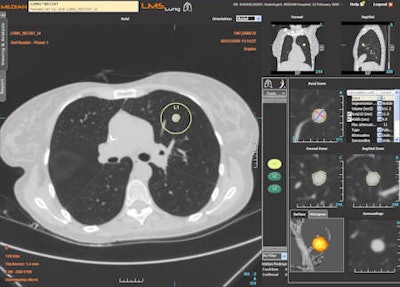

Follow-up of a pulmonary mass with the LMS platform (oncology imaging). Besides oncology imaging specialists, chest and abdominal radiologists will in the future use the software for pretreatment measurements after first detection of tumors. All images courtesy of Median Technologies.

Follow-up of a pulmonary mass with the LMS platform (oncology imaging). Besides oncology imaging specialists, chest and abdominal radiologists will in the future use the software for pretreatment measurements after first detection of tumors. All images courtesy of Median Technologies."LMS runs within PACS to find the same lesions at second examination follow-up, and measure and chart any changes. This saves the radiologist time; each follow-up CT evaluation process is 10 to 15 minutes faster than without using LMS," said Dr. Luis Martí-Bonmatí, La Fe's director of clinical imaging and president elect of the European Society of Gastrointestinal and Abdominal Radiology. "My feeling is that this automatic evaluation is more accurate and reliable as it doesn't suffer from interobserver variation."